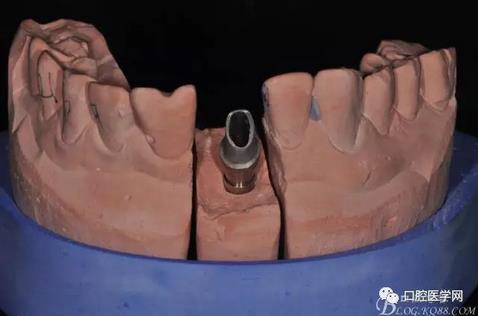

圖16 修復(fù)基臺(tái)模型頜面照

圖17 烤瓷冠唇側(cè)照